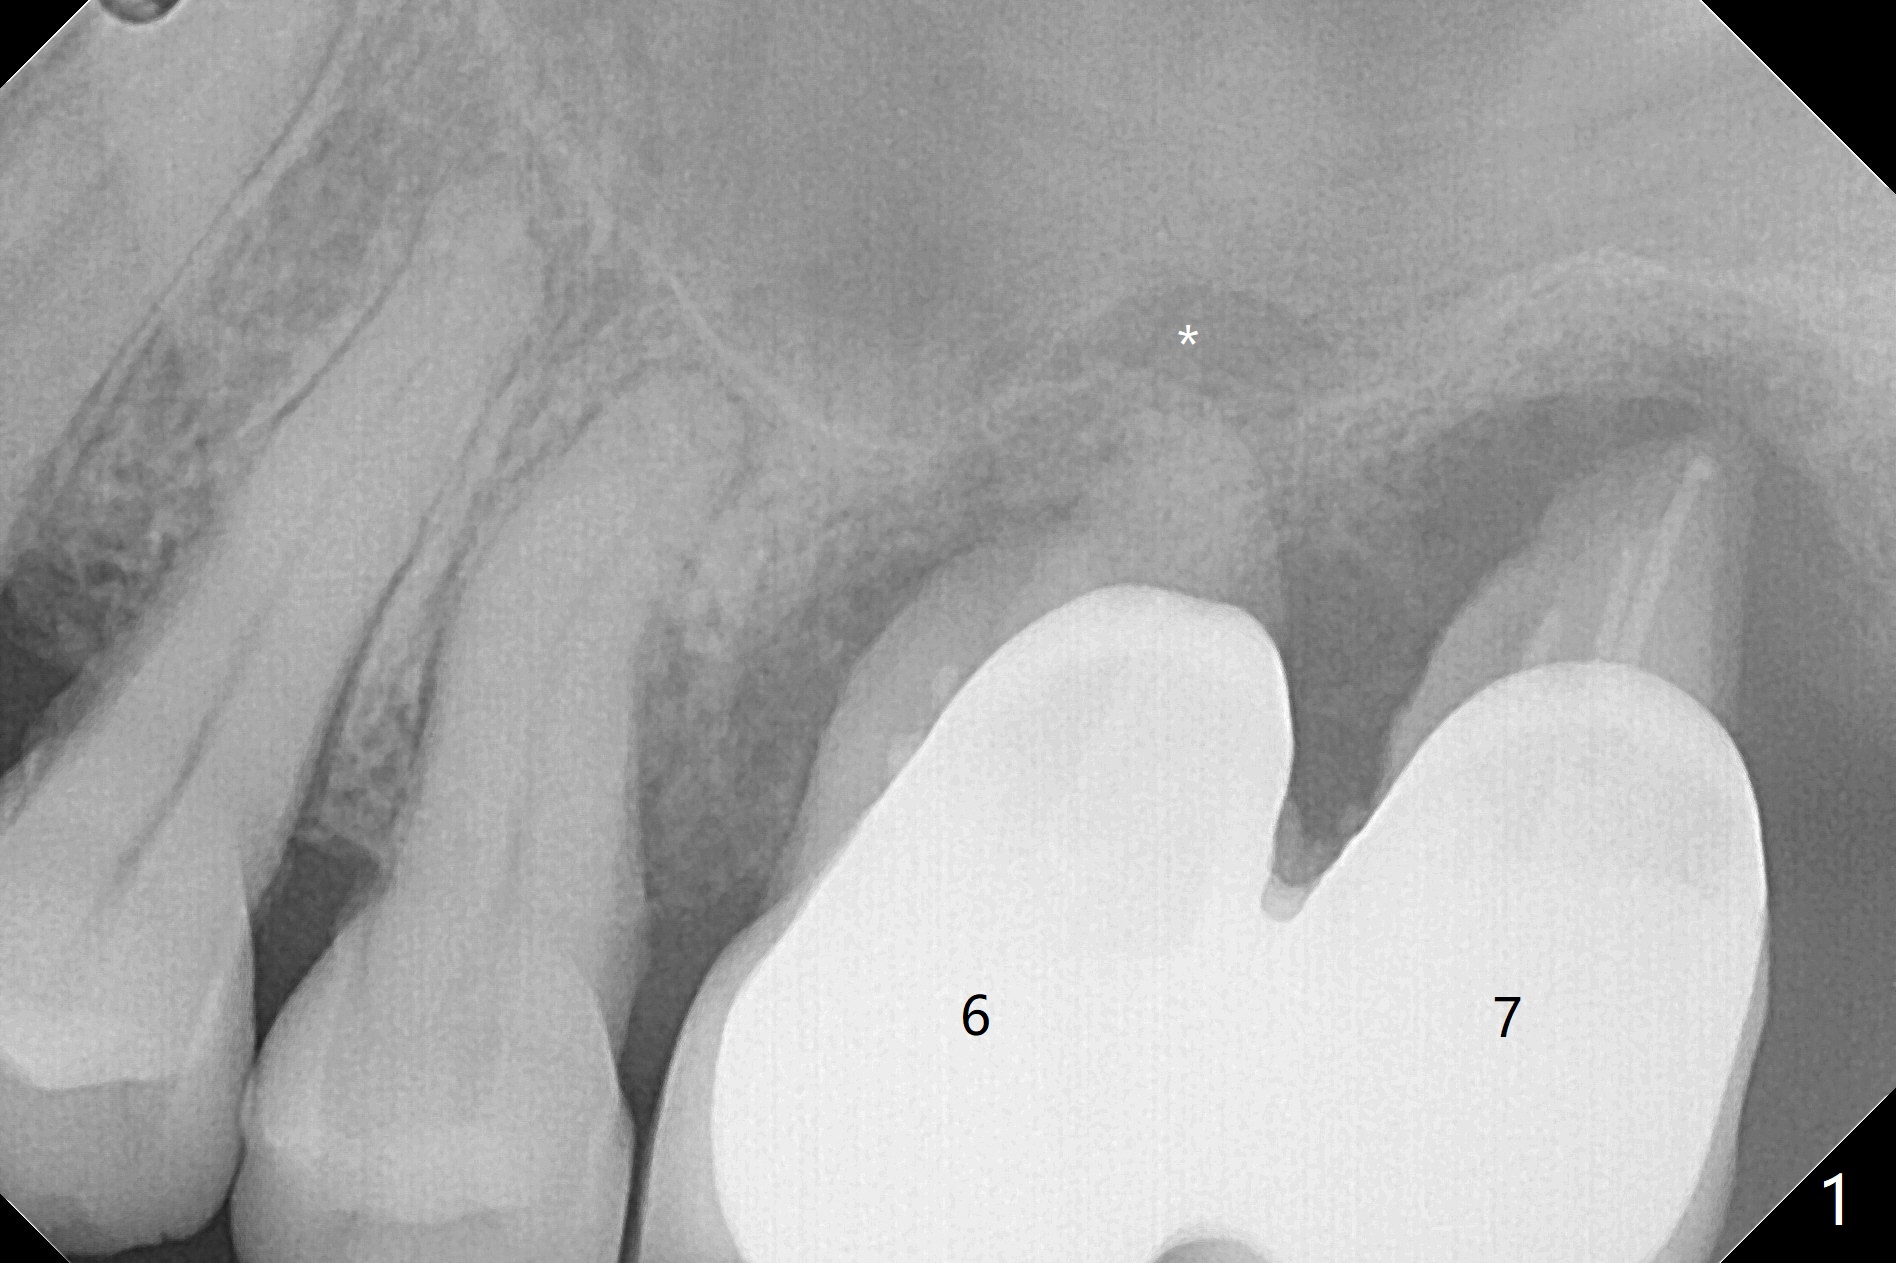

54岁女左上6,7连冠松动,牙槽窝大而敞开,似乎只有即刻植牙即刻修复能够固定粘性骨粉(抽血x2,图三),残余骨壁很薄(2-3 mm,图二),上颌窦内提升应该容易,使用Magic Sinus Lift Kit,其实6腭侧根可能已经进入上颌窦(图一:*)。两张PRF膜当中剪个洞,放置植体开口,然后插入基台,膜周围与牙槽窝开口接触,牙龈下1-2毫米,在膜下面再放置适当骨粉,膜表面放置湿纱布(防止树脂与膜粘合),然后制作临时牙冠。